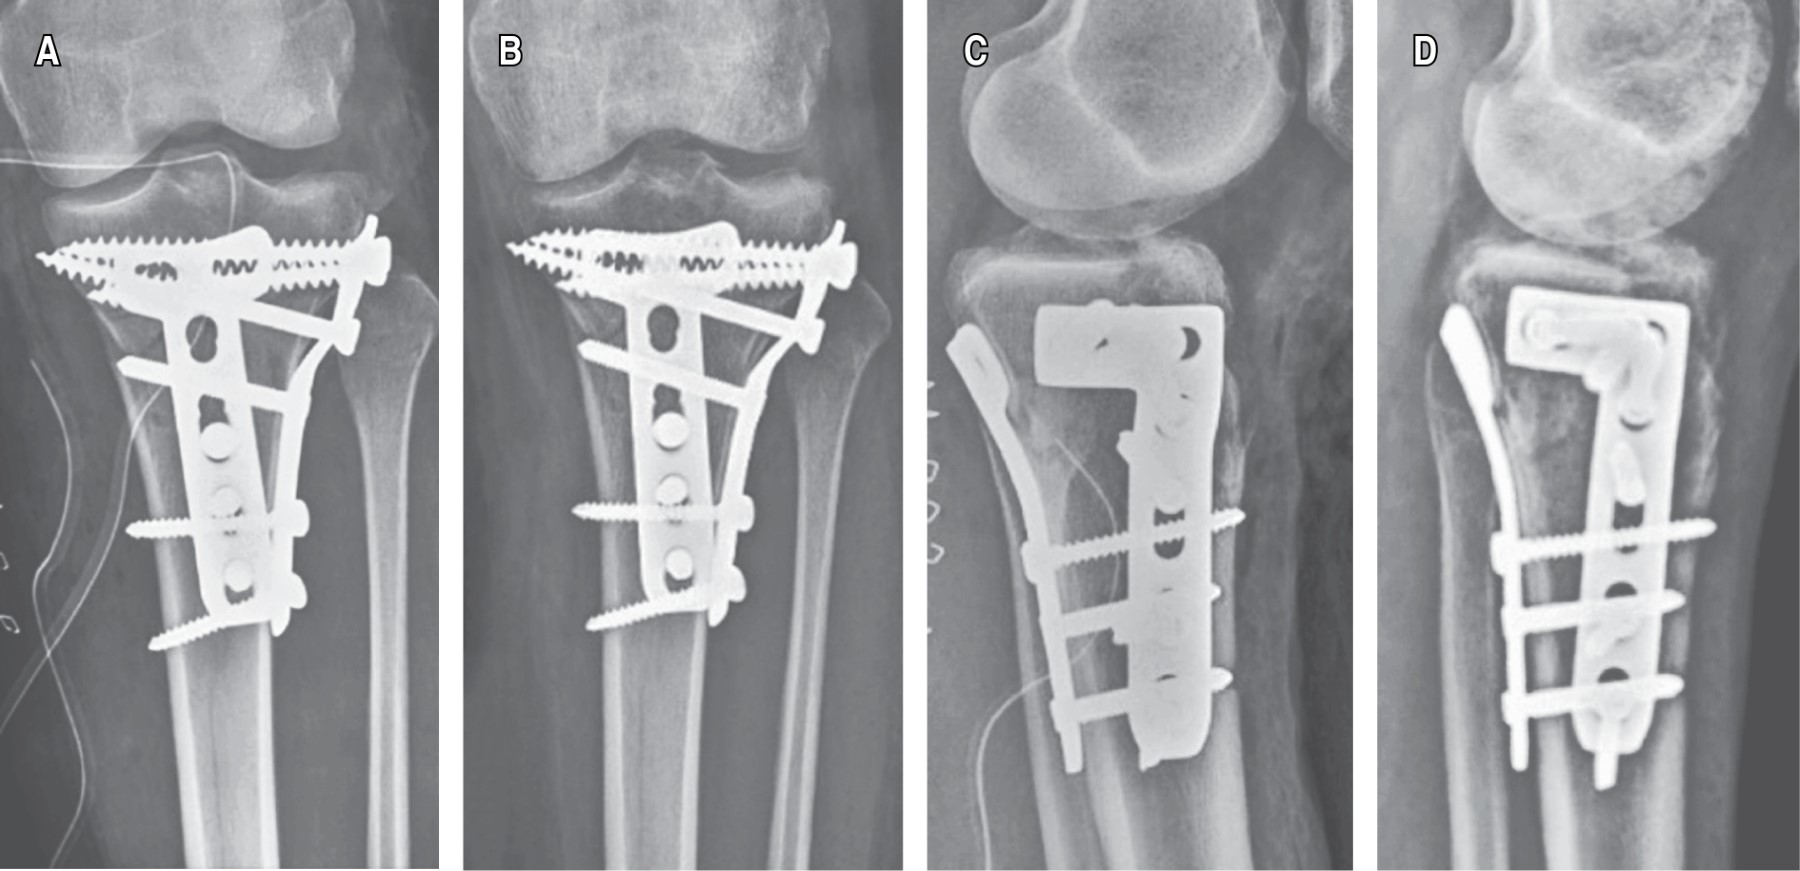

Se formaron dos grupos para comparación según el método de fijación utilizado. El grupo 1 (25 pacientes) fue tratado con reducción y fijación directa de columnas posteriores por medio de abordaje posterior de Lobenhoffer modificado (Figura 1) y placa bloqueada en T de 4.5 mm en conjunto con la fijación anterolateral o anteromedial, según los requerimientos de cada caso. El grupo 2 (42 pacientes) fue tratado con reducción y fijación indirecta de columnas posteriores por medio de abordaje anterolateral y/o anteromedial y fijación con placa bloqueada en L de 4.5 mm. En todos los pacientes se buscaron intencionalmente lesiones meniscales, realizando reparación con sutura en los casos necesarios.

GRUPO 1 (FIGURA 2) DESPLAZAMIENTO MPTA

Y PPTA DURANTE SEGUIMIENTO

Se observó un ligero aumento en el MPTA durante el seguimiento, que pudiera explicarse por una columna medial estable que no sufre colapso, en conjunto con un ligero colapso de platillo lateral en el plano coronal; sin embargo, este desplazamiento no alcanzó una magnitud significativa. En cuanto al PPTA, se observó una ligera disminución atribuible a colapso de columnas posteriores, manteniendo valores dentro de rangos de normalidad, siendo este colapso estadísticamente significativo. Estos cambios fueron menores a 1° en ambos planos.